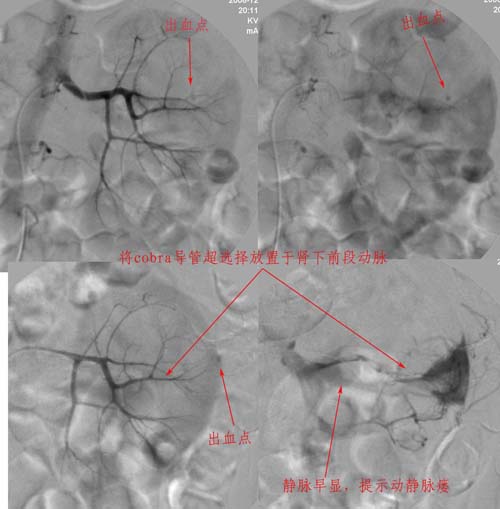

男性,45岁,因左输尿管与肾盂结合部结石住院治疗,经皮肾镜治疗失败后,改做开放手术.手术后3天出现血尿,5天保守治疗仍不能止血,申请肾动脉dsa,见下图片,发帖目的在于请各位分析判断出血部位.

介入治疗过程:

注:图5\6文字标示应为".....再次证实出血部位"

病史已说明肾盂和输尿管交界处结石,穿刺时首先经过包膜--肾实质--肾盂,这样就会有一潜在的通道,包膜下的出血可以延着通道渗入至肾盂、输尿管,所以就有血尿了。